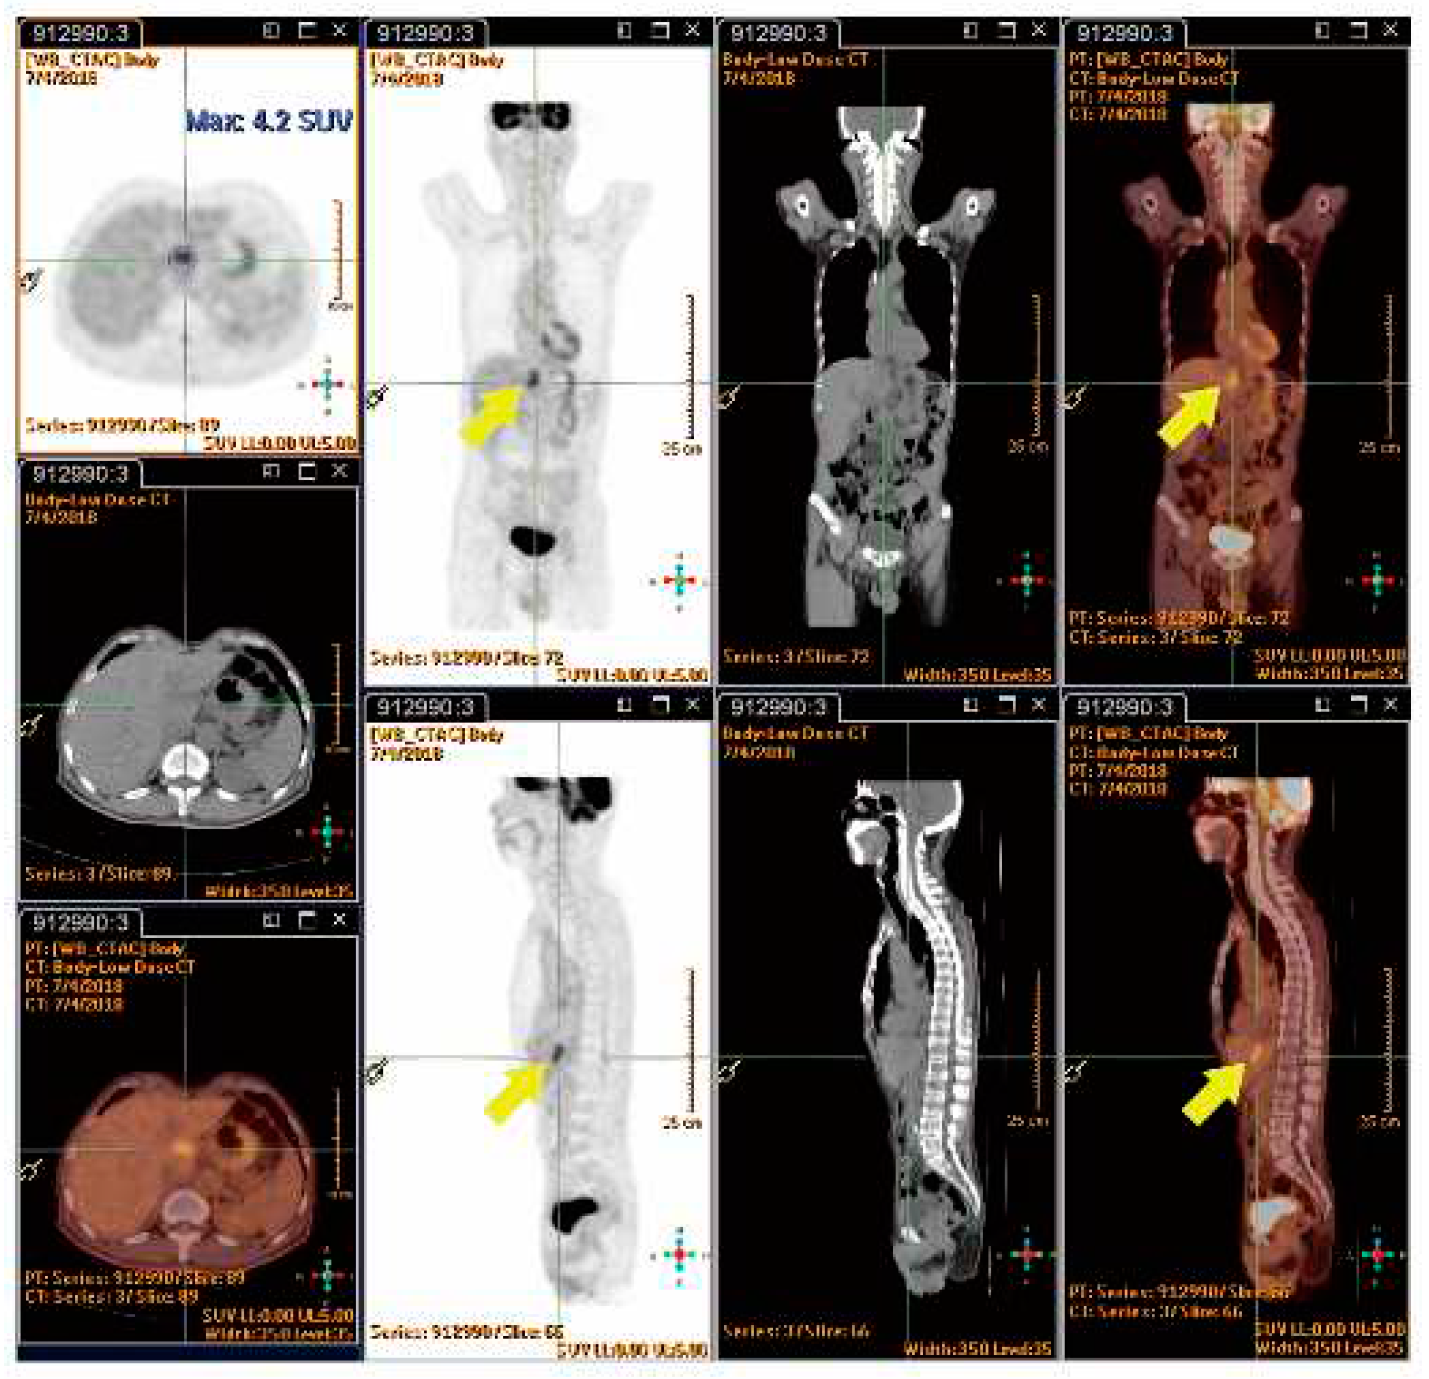

4.7.4. SUVmax value of PET/CT Serve as Indicator of RILD?